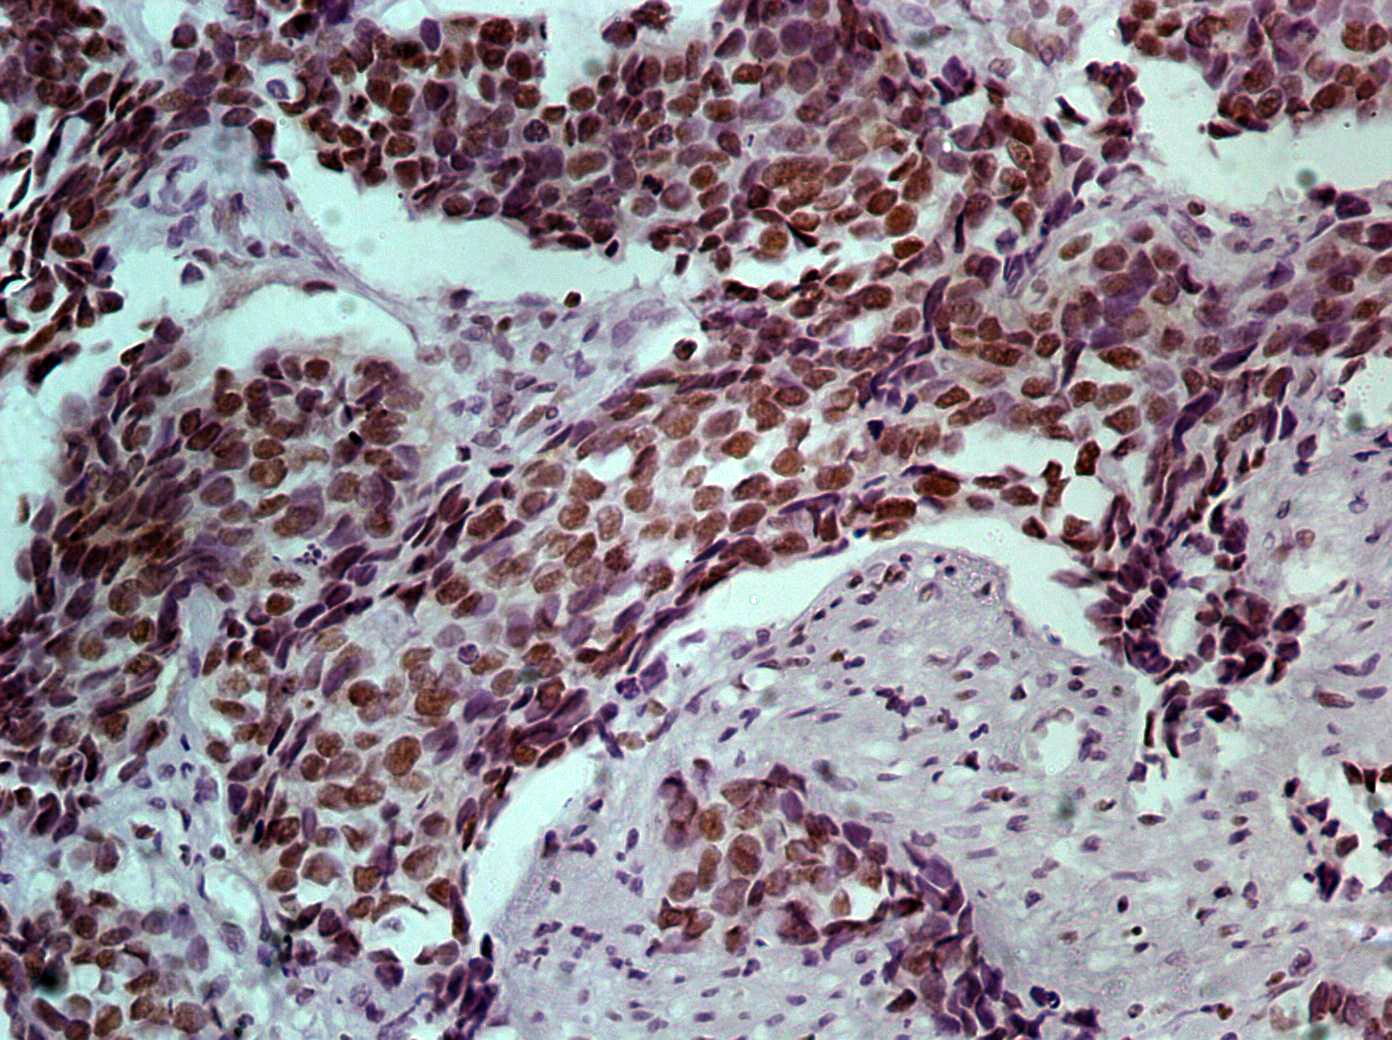

The fluoresceinated Hsa-miR-365A-3P probe has been designed from mature human miR-365A-3P sequence. This Hsa-miR-365A-3P identifies miR-365A-3P sequences in formalin-fixed, paraffin-embedded human tissues and freshly prepared frozen tissues by in situ hybridization. This probe does not react with normal human mRNA or nuclear DNA present in tissues.